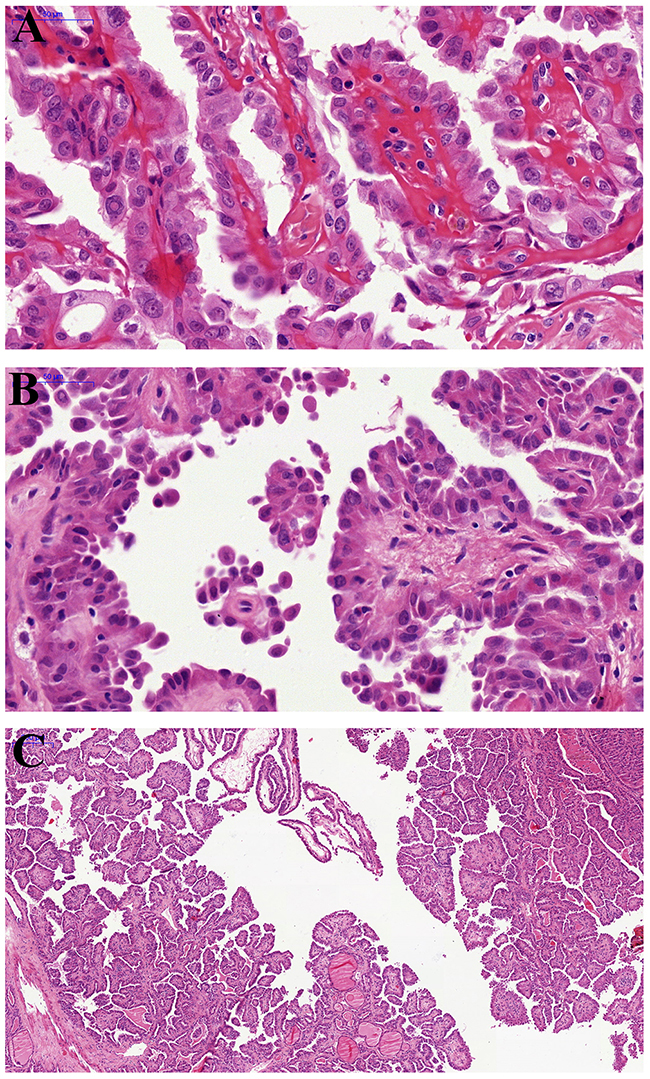

Table 1 shows the clinicopathological features of the HVPTC. The prevalence of HVPTC was 1.69% (18/1062) of all PTC diagnosed in our institution during the period of 2000-2010. The mean age was 41.8 years (range23-78years) with a clear female predominace (female/male ratio, 13:5). The mean tumor size was 2.53 cm (range1-5cm), with 3 being multifocal (16.7%). Morphologically, papillary and micropapillary structures and hobnail features were identified in all the 18 selected cases (Figure 1A, 1B and 1C). Focal (usually <10%) hobnail appearance was not unusual in some PTC cases, presented on the top of a papilla and the marginal area of the lesion, but we did not put these cases into this cohort due to the selected criteria that hobnail features must be observed in≥30% tumor cells. Extra-thyroidal extension and lymph-vascular invasion were observed in 6 (33.3%) and 2 (11.1%) patients, respectively, whereas lymph node metastasis was identified in 10 patients (58.8%). Hobnail features were not observed in any of our 12 ATC/PDTC cases.

Figure 1: Pathological findings of hobnail variant papillary thyroid carcinoma. (A) The papillary architecture and characteristic nuclear features of papillary carcinoma: pseudoinclusions and nuclear grooves. (B) Micropapillary structures lined by cuboidal cells with apically placed nuclei (“hobnail”appearance) and loss of cellular cohesion. (C) The papillary architecture with focal micropapillary areas at low magnification.